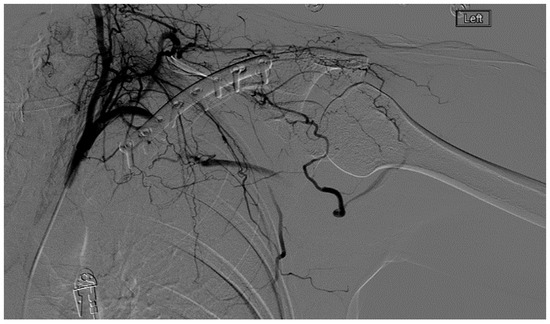

A 27 year-old female who had suffered a left clavicular fracture that was repaired previously presented with left upper extremity numbness and pain for one week. The symptoms occurred spontaneously and were intermittent throughout the week. She experienced no relief with analgesics. She presented to our Emergency Department. Brachial, ulnar and radial pulses were non-palpable. An arterial duplex revealed an occlusive thrombus of the brachial artery at the mid-humerus that appeared to be associated with the patient’s previous clavicular repair (Figure 5). A CT angiogram subsequently revealed a subclavian artery aneurysm adjacent to one of the screws from her prior clavicle repair (Figure 6).

Figure 5.

Arterial thoracic outlet syndrome (ATOS) patient with metal plate and screws after a prior clavicular fracture—the screws are abutting the thoracic outlet.

A heparin drip was then initiated, and she was taken to the catheterization lab for thrombolysis. This was carried out with Alteplase for 48 h as the patient had strong collaterals and was not in limb-threat (Figure 7, Figure 8, Figure 9, Figure 10 and Figure 11). However, her radial artery remained occluded. She was then taken to the operating room for thromboembolectomy of the left brachial and radial arteries (Figure 12). She was continued on anticoagulation post-operatively and was discharged.

Figure 7.

Left subclavian arteriography demonstrating a thrombosed brachial artery at the mid-humeral level and extensive collateralization proximally.